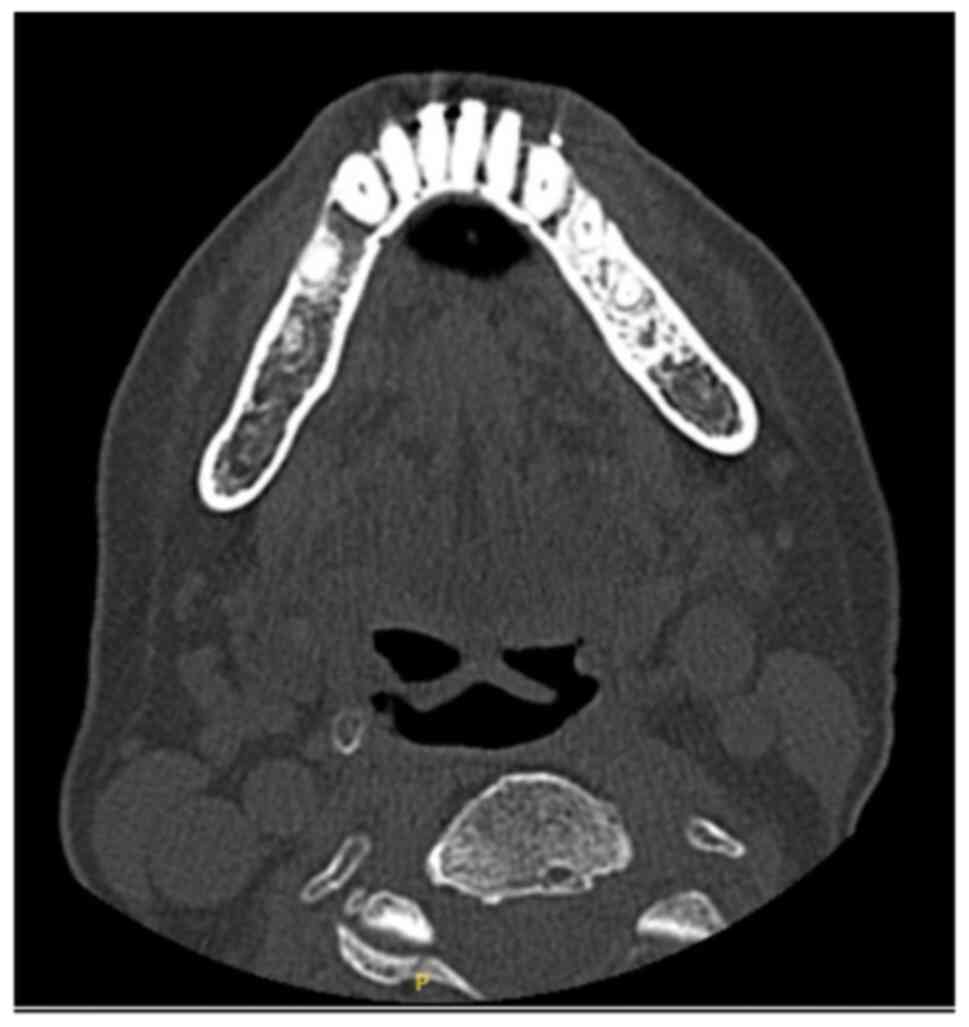

Methotrexate‑related other iatrogenic immunodeficiency‑associated lymphoproliferative disorder (MTX‑OIIA‑LPD) is prone to extranodal involvement but rarely involves the central nervous system (CNS). The present study reports a case of MTX‑OIIA‑LPD of the CNS discovered during medication‑related osteonecrosis of the jaw (MRONJ) treatment in a 76‑year‑old woman with rheumatoid arthritis (RA). The chief complaint of the patient was bone exposure and pain in the right mandibular molar. The patient had been receiving MTX for RA and alendronate sodium hydrate for osteoporosis, followed by denosumab. Treatment was initiated based on a diagnosis of MRONJ. However, the patient experienced lightheadedness and floating dizziness afterwards. Examinations revealed scattered neoplastic lesions in the brain. The histopathological diagnosis was diffuse large B‑cell lymphoma. A systemic search also revealed adrenal involvement. Since the patient was taking MTX, a diagnosis of MTX‑OIIA‑LPD was made and MTX was discontinued. Chemotherapeutic agents were administered since the central lesions became symptomatic. The MTX‑OIIA‑LPD lesions in the brain and adrenal glands completely resolved 8 months after onset. The physical condition of the patient improved, and the bone‑exposed areas became epithelialized. Reports on MTX‑LPD in the oral and maxillofacial region are few, which may delay its diagnosis. Therefore, biopsy of oral lesions in patients with MRONJ who are taking MTX and collaboration with related diagnostic departments, such as rheumatology and hematology, must be done to initiate the diagnosis and treatment of extraoral MTX‑LPD.